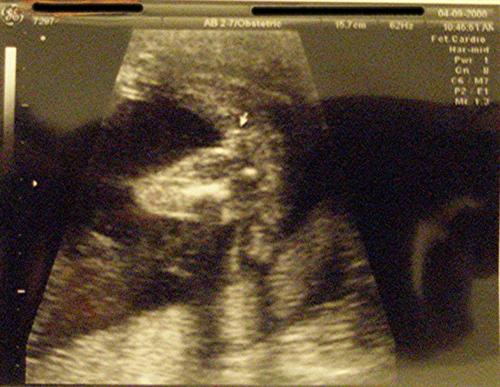

The Level 2 went well. Ed-lie Bubbles is measuring right on target. She is very healthy and moving around - tumbling and kicking - so much so that I may give her the last name "Tynes" in honor of the Giants' kicker who got them into the Superbowl. Here she is again:

THE MONEY SHOT: